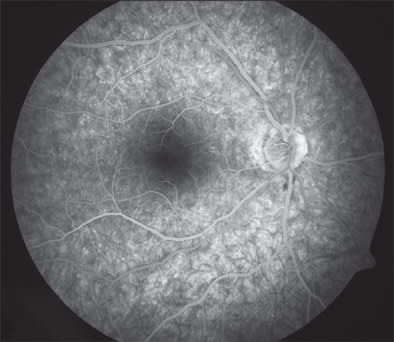

Inflammatory causes of photopsias are due to outer retinal or photoreceptor irritation from focal infection or inflammation. Flashes of light have been described in ocular toxoplasmosis7 and birdshot chorioretinopathy/vitiligo chorioretinopathy8 and in the spectrum of diseases that includes acute zonal occult outer retinopathy (AZOOR), multiple evanescent white dot syndrome (Figure 2), acute idiopathic blind-spot enlargement syndrome, punctuate inner choroidopathy, multifocal choroiditis and panuveitis, and acute macular neuroretinopathy.9-12 In AZOOR, photopsias are a frequent and important diagnostic symptom, accompanying visual loss or visual defects in up to 70% of eyes. Photopsias can either precede or follow onset of visual loss. They have been described as occurring in the field of the visual loss with the quality of flickering or shimmering.13 An antecedent viral-like illness has been described in association with the onset of most of these conditions.

Figure 2. Patient with multiple evanescent white-dot syndrome (MEWDS) and symptoms of unilateral photopsia.

Figure 3. Fluorescein angiogram of same patient with MEWDS demonstrating signature "wreath sign" (red circles).